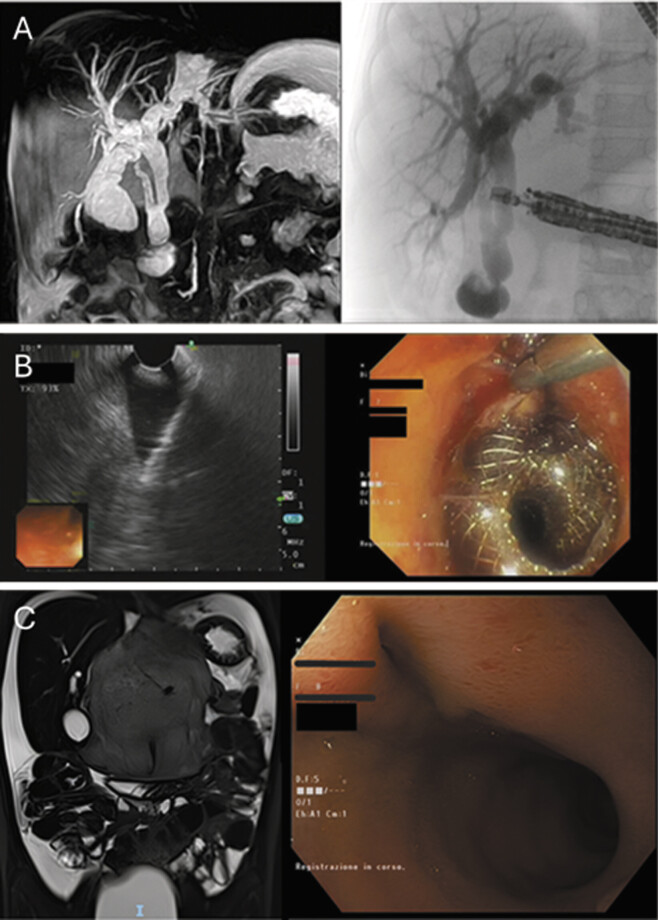

我们报告了一名6岁儿童在腹部神经母细胞瘤(NB)切除术中因术中损伤而继发的胆总管(CBD)造口后狭窄的应用内镜胆囊十二指肠吻合术。患者被诊断为M期NB,特点是骨髓和椎骨播散,MYCN扩增。经过多个周期的化疗和随后的造血干细胞移植,患者计划手术切除。术前影像学检查确定了几个影像学确定的危险因素,包括肝门浸润和十二指肠胰复合体浸润。在切除肿瘤过程中,发生了CBD的意外损伤,随后通过端到端吻合修复。术后7个月,患者因吻合口狭窄而出现梗阻性黄疸,通过在扩张的胆囊和十二指肠之间放置超声内镜引导的腔内金属支架(LAMS)成功控制。根据我们的经验,内镜胆囊十二指肠吻合术是解决小儿术后医源性CBD狭窄的一种新方法。有必要进一步研究以阐明其益处和风险,并评估其长期疗效和更广泛应用的潜力。

We report the use of endoscopic cholecystoduodenostomy in a 6-year-old child to manage postanastomotic stricture of the common bile duct (CBD) secondary to an intraoperative injury sustained during the resection of an abdominal neuroblastoma (NB). The patient was diagnosed with stage M NB, characterized by dissemination to the bone marrow and vertebrae, and MYCN amplification. Following multiple cycles of chemotherapy and subsequent hematopoietic stem cell transplantation, the patient was scheduled for surgical resection. Preoperative imaging identified several image-defined risk factors, including infiltration of the porta hepatis and of the duodenopancreatic complex. During the dissection of the tumor, an incidental injury to the CBD occurred, which was subsequently repaired via end-to-end anastomosis. Seven months postoperatively, the patient presented with obstructive jaundice due to an anastomotic stricture, which was successfully managed through the placement of an endoscopic ultrasound-guided lumen-apposing metal stent (LAMS) between the dilated gallbladder and the duodenum. In our experience, endoscopic cholecystoduodenostomy constitutes a novel approach for addressing postoperative iatrogenic CBD strictures in pediatric patients. Further research is warranted to elucidate its benefits and risks as well as to evaluate its long-term efficacy and potential for broader application.